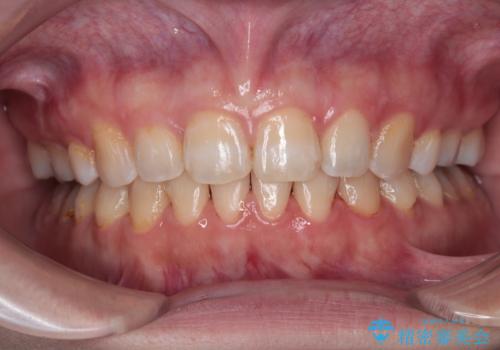

インビザラインによる狭窄歯列の拡大矯正

- 前歯のデコボコを治したいとのことで来院された患者様です。

上下顎ともに歯列全体の後方移動と側方拡大、IPR(歯と歯の間を削る)によってデコボコが解消するように設計し、インビザラインにより治療を行うこととしました。

後方移動に際し、上下の親知らずは4本とも抜歯することとしました。

治療途中で関西に転勤となってしまったため、東京に出張で来るタイミングに合わせて治療を進めることになりました。そのため、治療期間が長くなってしまいましたが、無事に仕上げることができました。